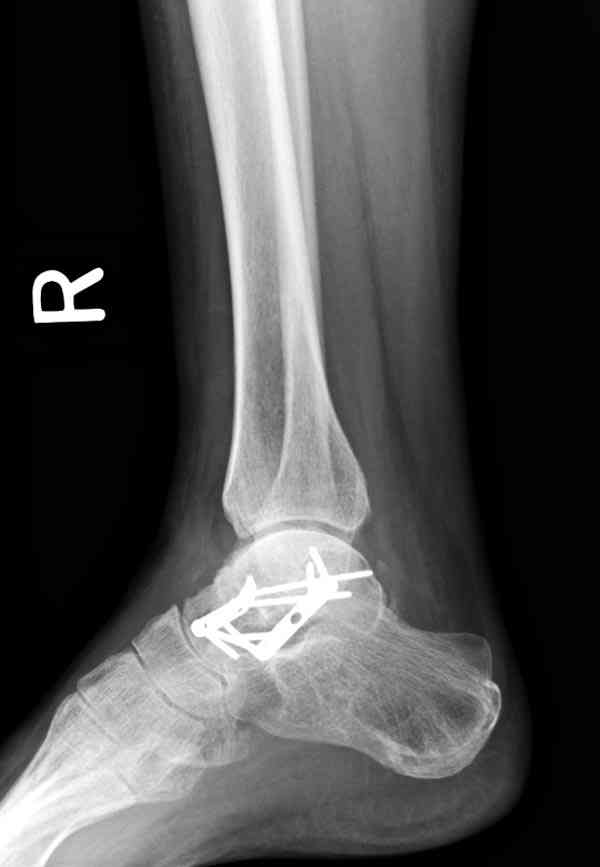

Случай с множественным оскольчатым переломом тарана оперированный из двойного доступа.

Через 8 мес.: